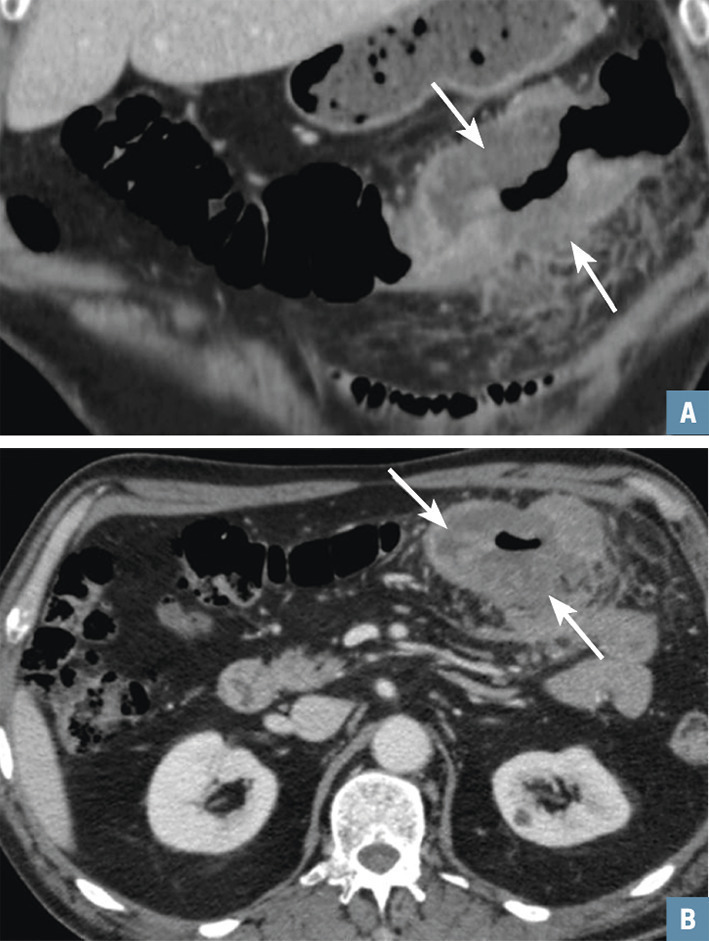

Un patient de 25 ans consulte pour des douleurs abdominales de la fosse iliaque droite. Pas de fièvre, CRP à 15. L’échographie abdominale est normale mais l’appendice n’est pas visible. Le scanner avec injection met en évidence, au temps portal, en arrière du cæcum, une structure tubulée borgne correspondant à l’appendice tuméfié, à paroi épaissie, intensément rehaussé (fig. 2 ; flèche blanche) avec infiltration de la graisse péri-appendiculaire (flèche noire). Le diagnostic d’appendicite aiguë rétro- cæcale est posé. L’échographie a été prise à défaut par la topographie atypique.

Un homme de 68 ans se plaint d’une altération de l’état général avec troubles du transit d’apparition récente et douleurs abdominales. Le scanner avec injection au temps portal montre un épaississement pariétal marqué du côlon transverse circonférentiel, bourgeonnant, avec contours irréguliers (fig. 3 ; flèches blanches). La graisse du méso est infiltrée au contact. On pose le diagnostic de cancer colique. La biopsie faite lors de la coloscopie le confirme : c’est un adénocarcinome.

Un homme de 68 ans se plaint d’une altération de l’état général avec troubles du transit d’apparition récente et douleurs abdominales. Le scanner avec injection au temps portal montre un épaississement pariétal marqué du côlon transverse circonférentiel, bourgeonnant, avec contours irréguliers (